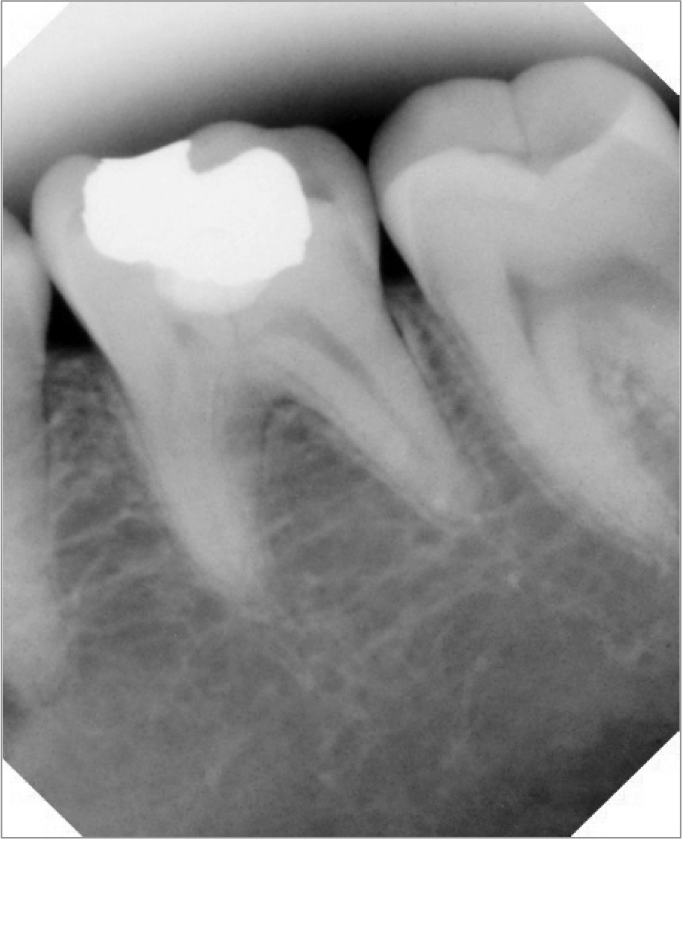

A system that prevents x-ray backscatter emits less radiation. Further, consistently good images due to receptive and efficient backing that captures x-rays across a dynamic range of settings and images that can be enlarged and enhanced without using pixilation enable doctors to capture excellent images to view and show (Figure 2 and Figure 3).

Figure 2 and Figure 3. The enhancement tools available with many digital imaging systems can help bring to light anatomic detail to increase diagnostic accuracy and case acceptance.